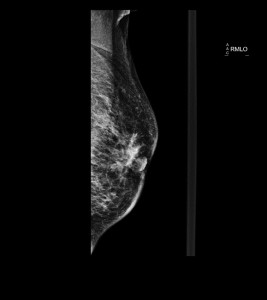

Ante la sospecha de cáncer de mama en mujeres de más de 35-40 años la prueba de elección será la mamografía. Se realizan dos proyecciones, craneocaudal (CC) y oblicuo mediolateral (OML), que combinadas nos permiten localizar mejor la lesión.

Haz click en las imágenes para verlas ampliadas